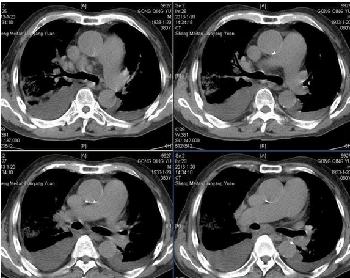

在现代科学中,胸部CT扫描是衡量人体体征的极好方法,胸部是许多重大疾病迹象的第一现场,简单的扫描就可以揭示人体内脏的各种状态。

来自澳洲的科学家们利用计算机模拟算法,对48名60岁以上成年人的胸部CT进行分析与数据对比(已知生死的旧数据),进而预测出实验对象在五年内甚至更久远的死亡率。事实证明,其精确度高达70%,甚至超过人类的预测结果。

首席研究员Luke Oakden-Rayner博士表示,虽然患者样本较少,但研究结果表明,计算机已经具备准确分辨疑难疾病的成像特点,目前尚有12000名参与者正在进行着类似的研究。